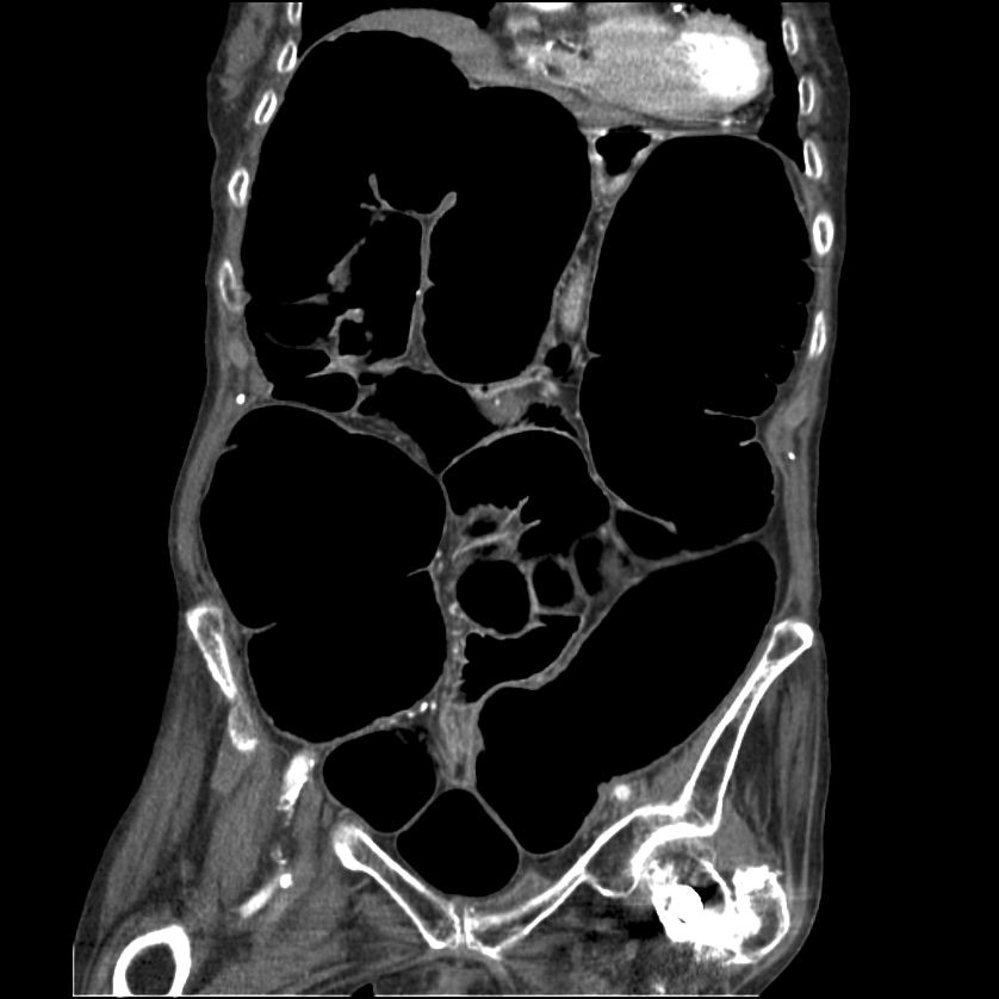

• Plain X-ray or CT scan showing marked colonic dilation, loss of haustra, and possible mucosal ulceration

• X-ray or CT scan: Colonic distention (> 6 cm dilation of the right colon and > 9 cm in cecum), loss of normal haustral pattern, irregular mucosal pattern with areas of ulceration alternating with areas of edema.